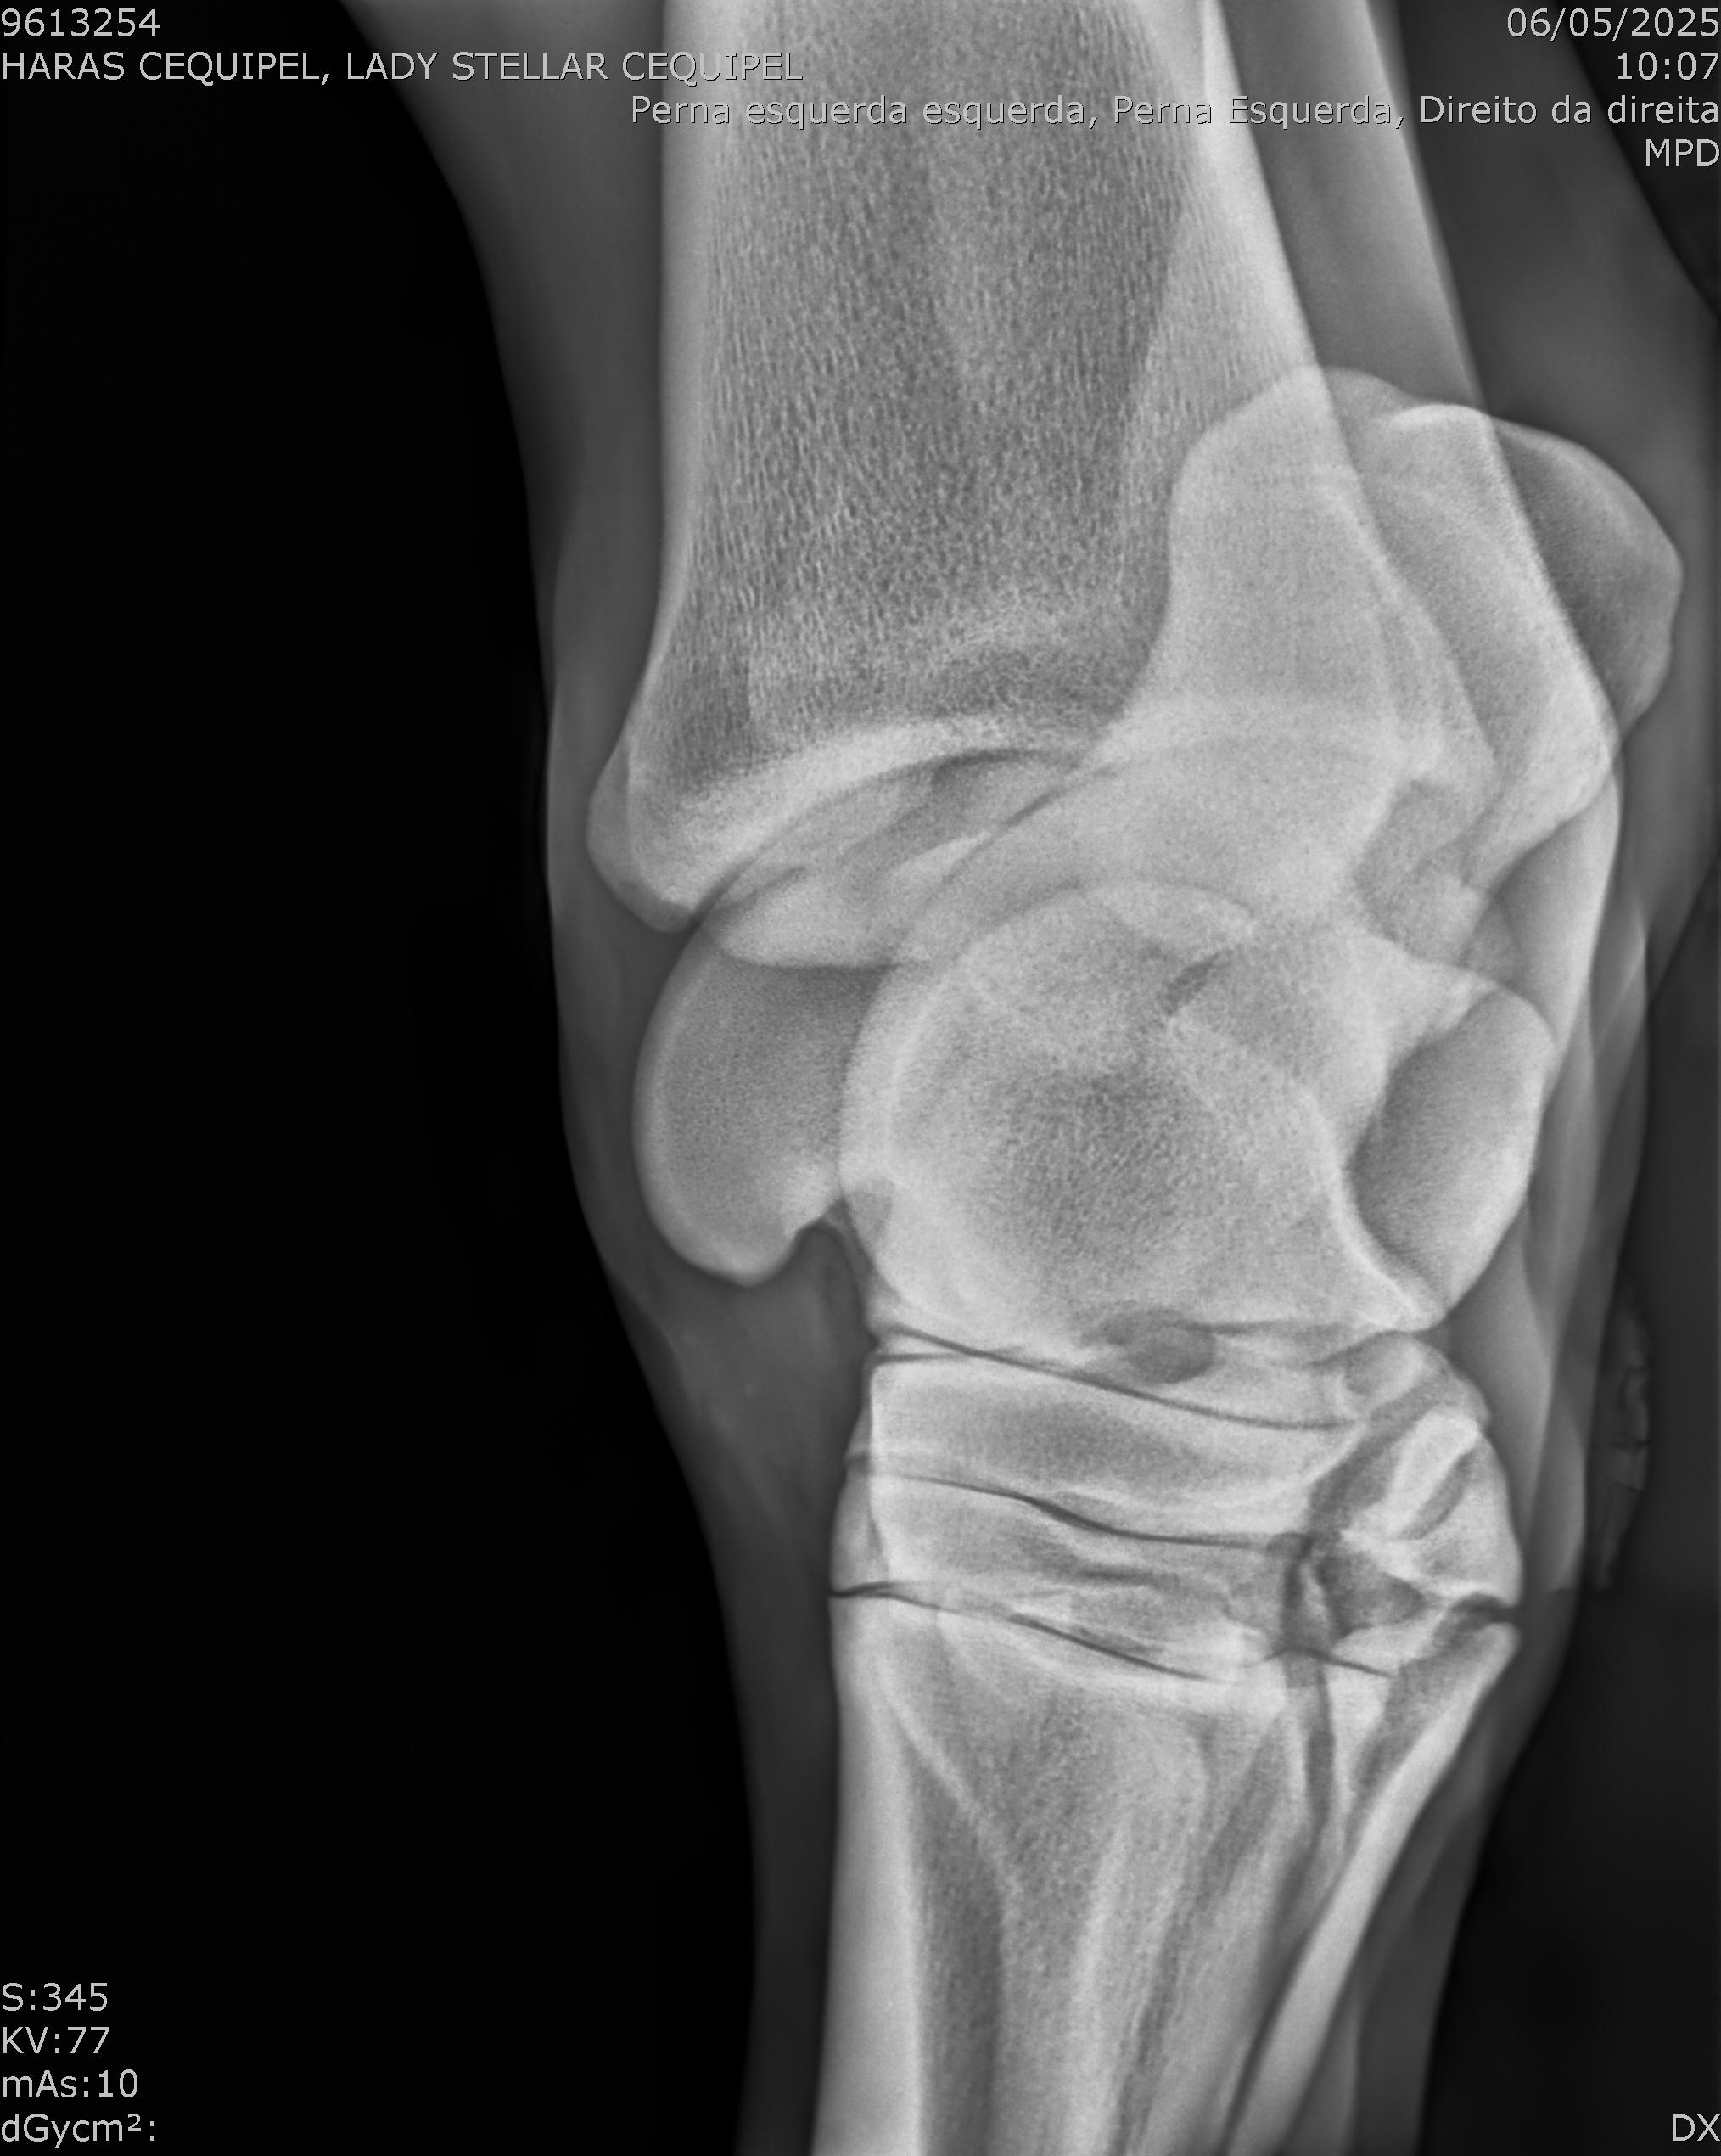

:: RAIOS-X DO LOTE